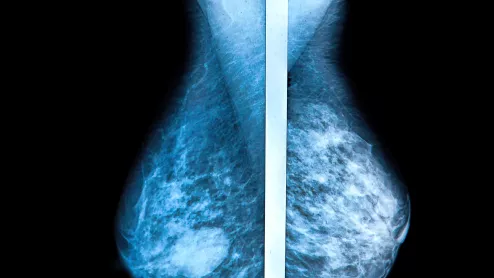

The European Union has certified AI software for reading mammograms, clearing the way for a South Korea-based AI vendor to sell another of its AI products across the European Economic Area.